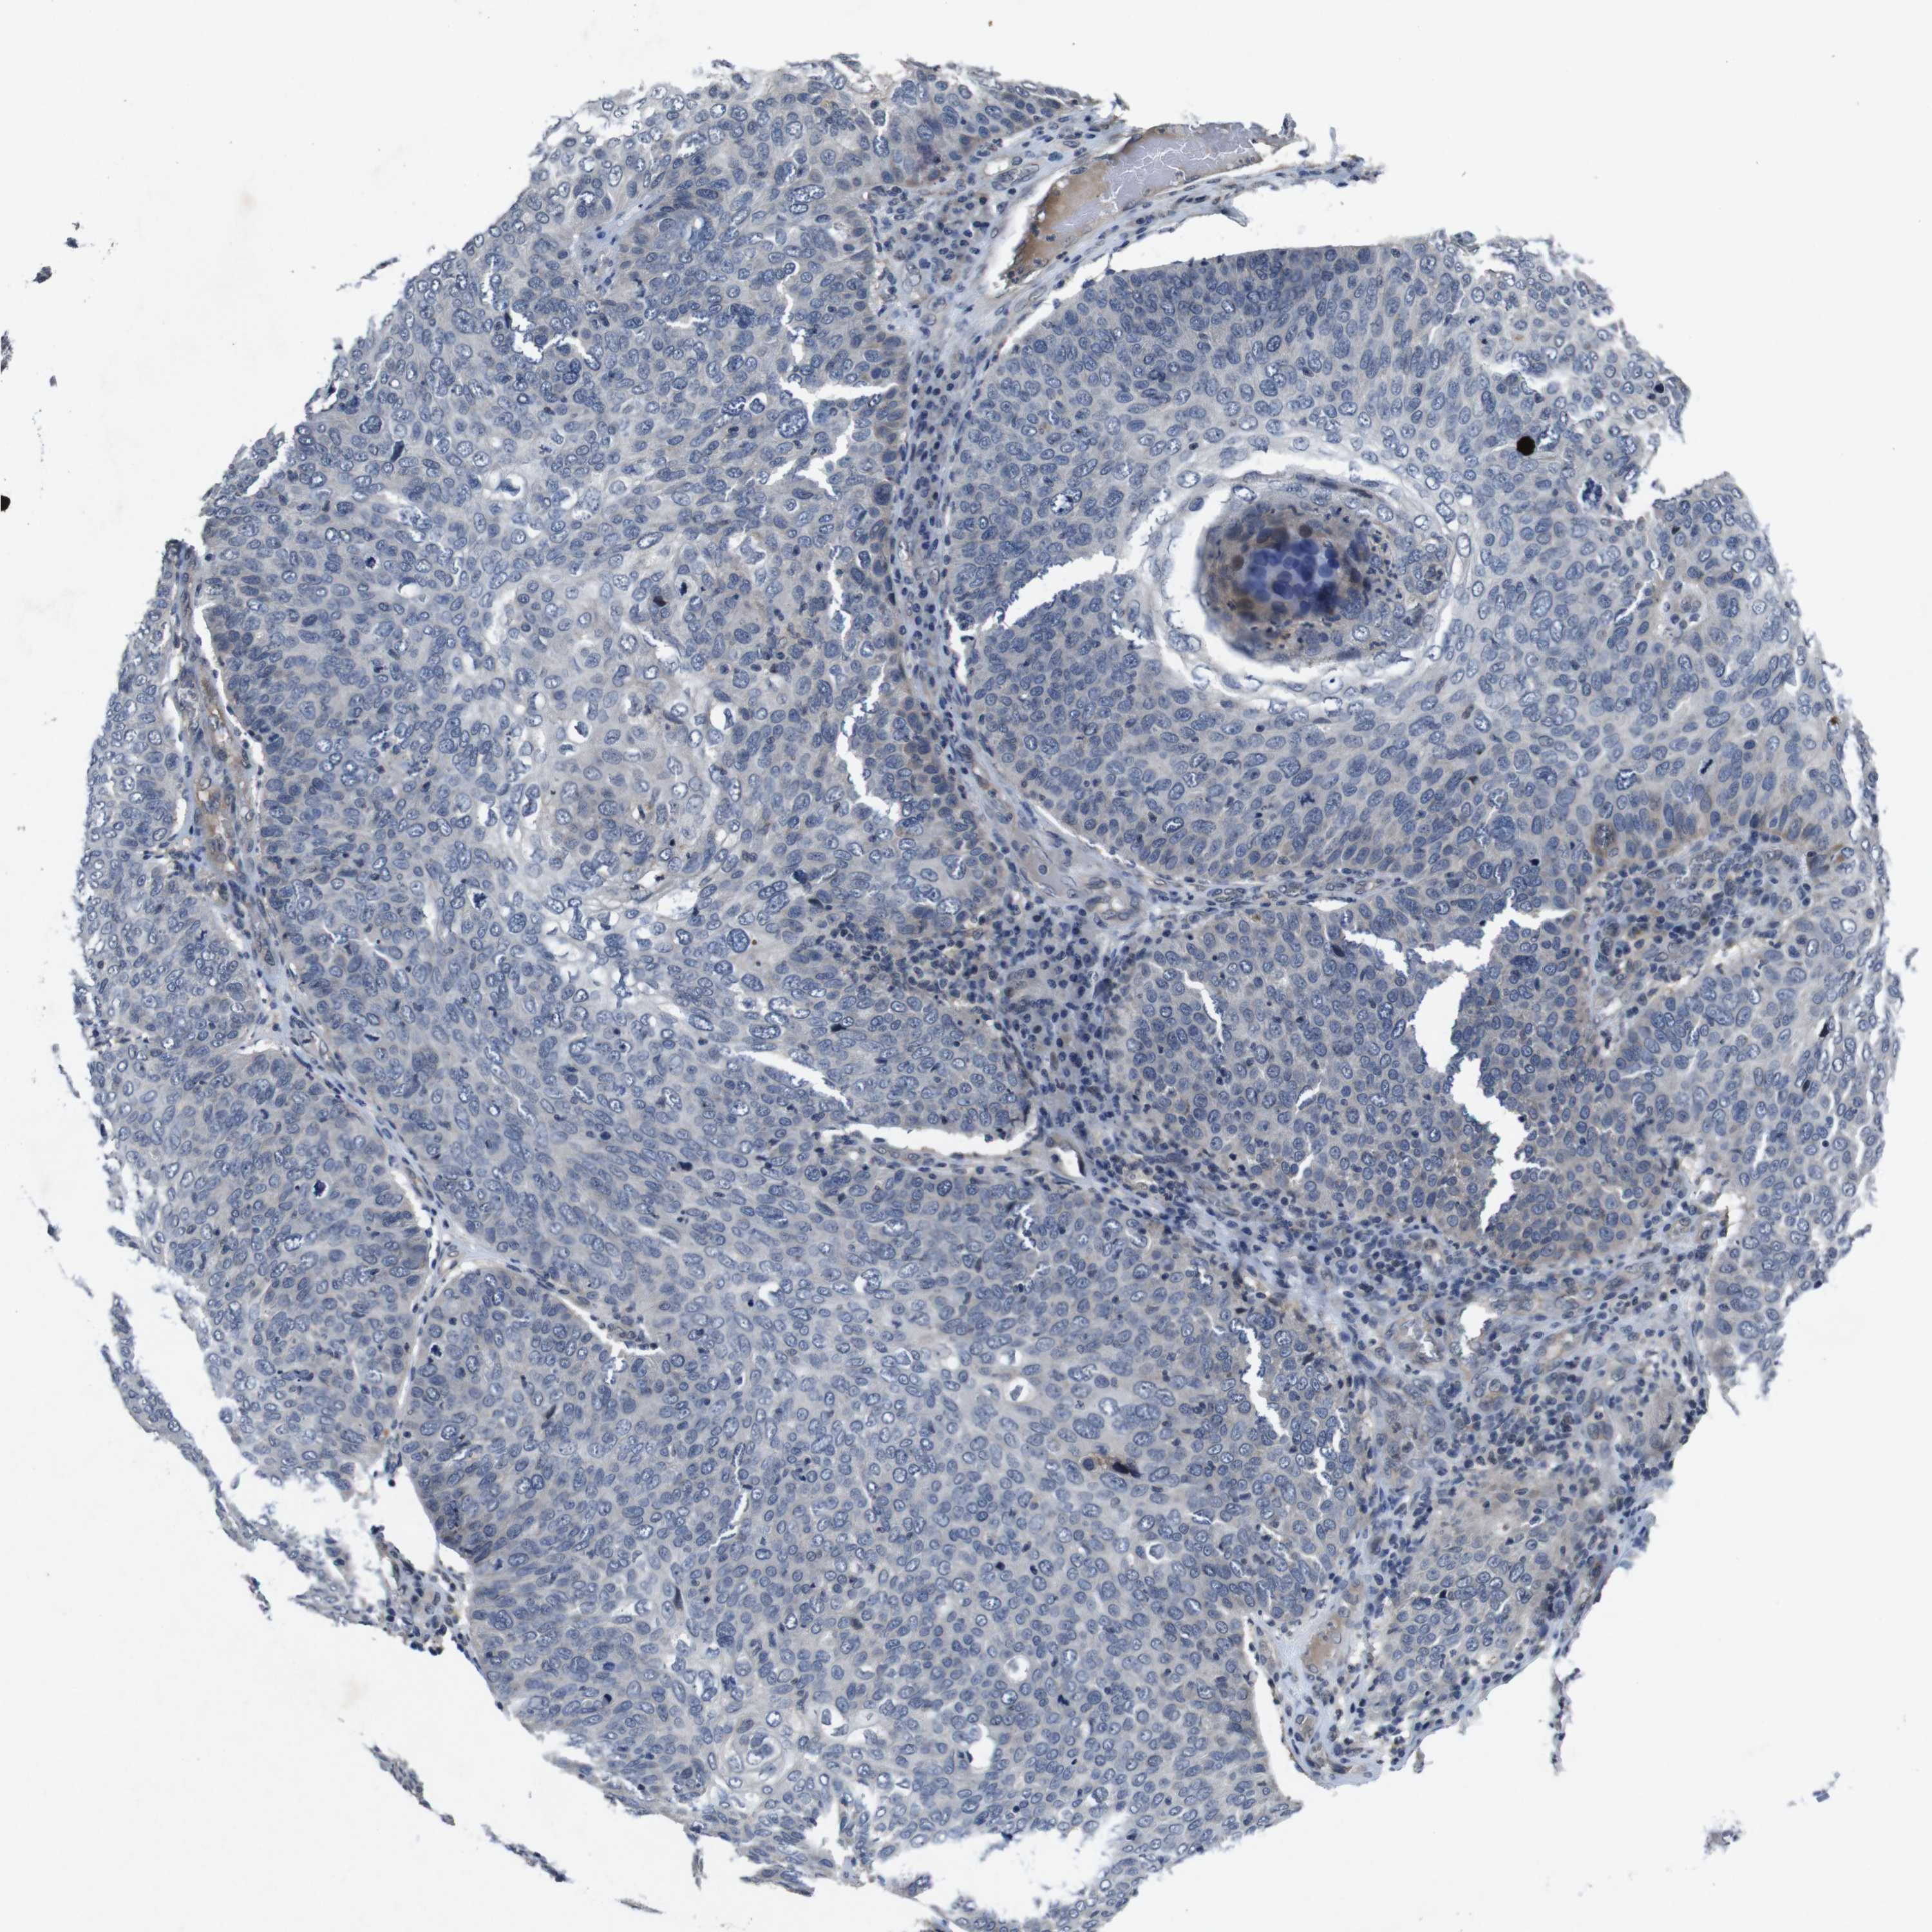

SKIN CANCER - Protein expressioni

A mouse-over function shows sample information and annotation data. Click on an image to view it in a full screen mode. Samples can be filtered based on level of antibody staining by selecting one or several of the following categories: high, medium, low and not detected. The assay and annotation is described here.

Antibody stainingi

Antibody staining in the annotated cell types in the current human tissue is reported as not detected, low, medium, or high, based on conventional immunohistochemistry profiling in selected tissues. This score is based on the combination of the staining intensity and fraction of stained cells.

Each image is clickable and will lead to virtual microscopy that enables deeper exploration of all samples and also displays staining intensity scores, fraction scores and subcellular localization as well as patient and tissue information for each sample.

Antibody CAB013090

Squamous cell carcinoma, NOS